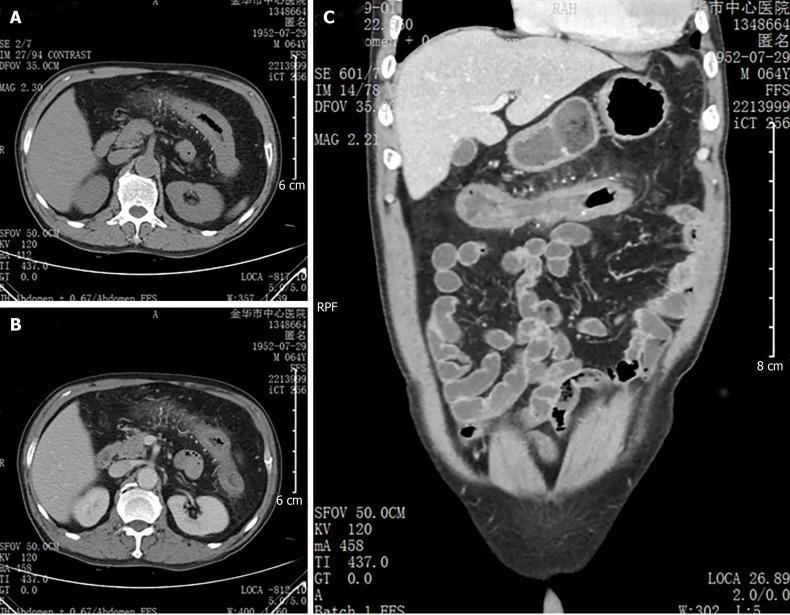

A 64-year-old man was referred to our department from his primary hospital because of abdominal pain, diarrhea, and fever for almost 10 d. Computed tomography showed colon wall thickening, with threadlike calcifications in the mesenteric vein in the transverse colon. Colonoscopy revealed purple-blue mucosa with multiple ulcers in the ascending and transverse colon. Biopsy showed thickening and calcification of the vein walls, perivascular and mucosal collagen degeneration, and amyloidosis. The patient had been consuming Chinese medicinal liquor, mainly that made from gardenia fruit, for 10 years. Based on these results, a diagnosis of MP with amyloidosis was made. After conservative treatment, the patient's discomfort subsided and he was followed closely. The use of Chinese herbal medicine was suspected to play a role in the pathogenesis of MP.

一名64岁男性因腹痛、腹泻和发热近10天从基层医院转诊至我科。计算机断层扫描显示结肠壁增厚,横结肠肠系膜静脉有丝状钙化。结肠镜检查显示升结肠和横结肠黏膜呈紫蓝色,有多处溃疡。活检显示静脉壁增厚、钙化及血管周围和黏膜胶原变性,还有淀粉样变性。该患者饮用中药酒(主要由栀子果实制成)已有10年。基于这些结果,诊断为伴有淀粉样变性的MP。经过保守治疗,患者的不适症状缓解并接受密切随访。怀疑使用中草药在MP的发病机制中起作用。